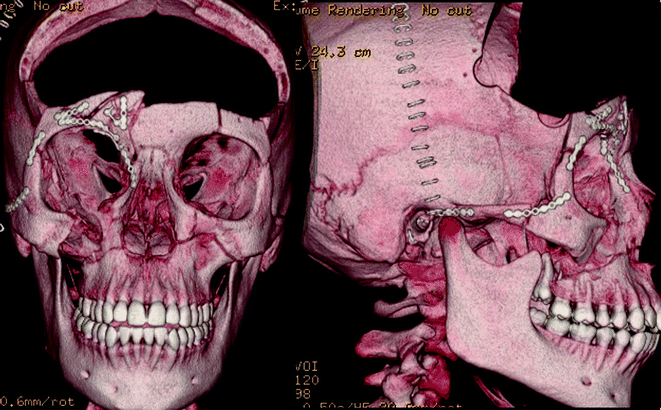

Fig. 19.13

Postoperative three-dimensional reconstruction demonstrating cranial decompression, reconstruction of zygomatic, maxillary, orbital bandeau, and orbital roof fractures

Fig. 19.14

Fig. 19.15

There are several intra-operative details that should be considered in conjunction with OMFS, Plastics, ENT and Oculoplastics teams to achieve several goals at the time of surgery: (1) decompression of cranial contents if there is a mass lesion or malignant edema, (2) primary repair of dural injuries using autograft, allograft, or dural substitutes, (3) reconstruction of anterior fossa floor and orbital bandeau, (4) thorough cranialization and exenteration of the frontal sinus, (5) reconstruction of severe, displaced facial and orbital injuries. A bicoronal incision was made and the subgaleal space was dissected anteriorly to the superior orbital rim, keeping the pericranium intact. A vascularized pericranial pedicle was incised beyond the incision posteriorly and up to the superior temporal line bilaterally; the pedicle was carefully dissected anteriorly to the superior orbital rim as well. This maneuver is critical for obtaining a large, vascularized autograft used for dural repair and reconstruction of the anterior fossa floor. A wide bifrontal craniotomy was performed, preserving the orbital bandeau to provide a scaffold for repairing her orbito-facial fractures. Her severe, depressed frontal sinus fracture was elevated and then cranialized and exenterated. The nasofrontal ducts were involuted and packed with muscle, bone chips, fat, and fibrin glue. A 7 cm dural laceration was present that extended from the frontal pole to the anterior clinoid process. The dura was elevated from the anterior fossa floor to visualize the extent of dural injury, and the orbital roof was internally reduced. The uninterrupted dura was opened and reflected medially; the anterior falx was dissected from the crista gali with suture ligation of the anterior superior sagittal sinus. A piece of pericranial graft was harvested far from the laceration site, and the dura was primarily repaired with 4-0 Nurulon suture. The orbital bandeau was carefully reconstructed to provide a scaffold for cranial reconstruction in the future. The remaining vascularized pericranial pedicle was laid on top of the reconstructed bandeau and sutured to the dura at the anterior clinoid process to avoid retraction of the pedicle. The dura was covered with moist gauze and the OMFS team reduced and plated her complex facial fractures. The frontal lobes at the time of closure were soft and demonstrated normal pulsations.